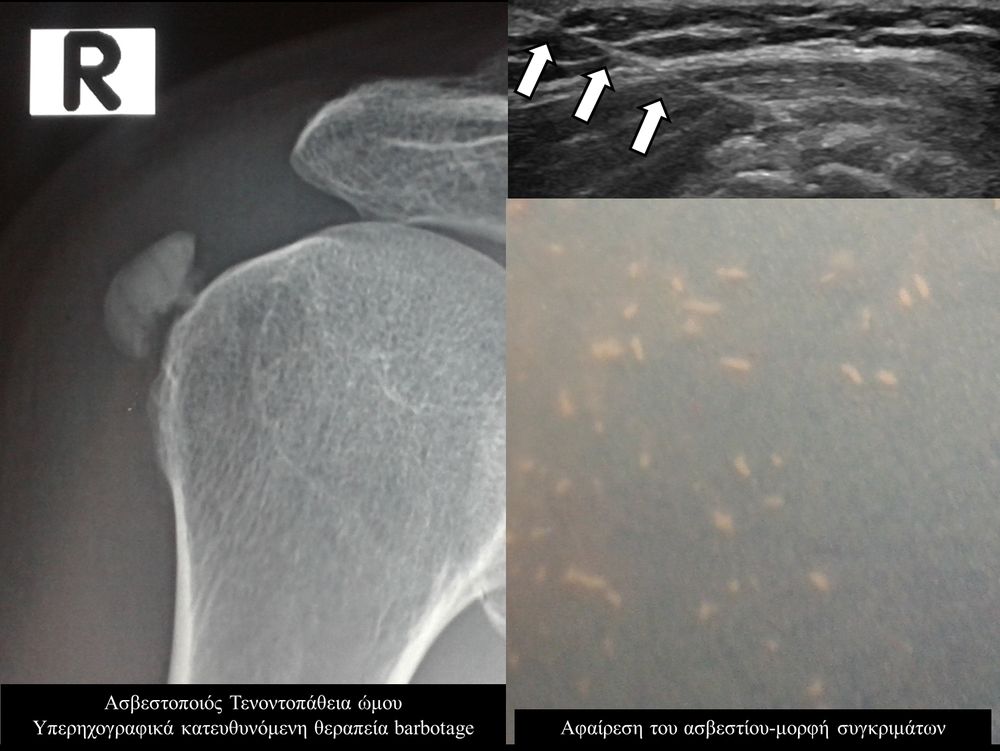

Η ασβεστοποιός τενοντοπάθεια-τενοντίτιδα είναι η εναπόθεση αλάτων ασβεστίου μέσα στους τένοντες,πιο συχνά του στροφικού πετάλου του ώμου, με αποτέλεσμα την τοπική φλεγμονή και πιθανή ρήξη του τένοντα.

Η υπερηχογραφικά καθοδηγούμενη αφαίρεση των επασβεστώσεων (barbotage) είναι μια ελάχιστα παρεμβατική (minimally invasive) τεχνική θεραπείας για την ασβεστοποιό τενοντοπάθεια. Με τους υπερήχους είναι δυνατός ο εντοπισμός των ασβεστώσεων και η διαδερμική τοποθέτηση μιας βελόνας στο κέντρο της συμπτωματικής ασβέστωσης. Στη συνέχεια γίνεται διαδερμικός τρυπανισμός και επαναλαμβανόμενες πλύσεις του ασβεστίου, με αποτέλεσμα τόσο την αφαίρεση της παθολογικής επασβέστωσης όσο και την αυξηση τοπικά της αιμάτωσης με αποτελεσμα την σταδιακή απομάκρυνση των παραγόντων φλεγμονής-ερεθισμού.